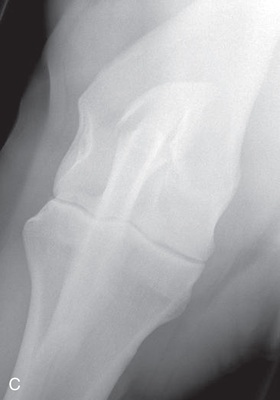

| Stifle | Lateromedial (LM) | Lateral (L) |

| Caudoproximal-craniodistal (CdPr-CrDi) | Caudocranial (CdCr) | |

Radiography of the femorotibial joint (stifle) is difficult because of the thickness of the surrounding tissue and the sensitive nature of this region. Because of the depth of the muscle in the femoral region, the caudocranial projection demonstrates little above the joint space. Radiographs of this region should be attempted only if the patient is cooperative. Safety is paramount in radiography of the hind region of the horse. Sedation or a twitch may be used; general anesthesia is also to be considered.